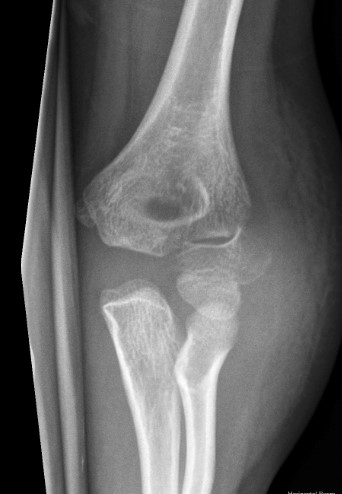

X-ray

Undisplaced

- typically metaphyseal flake

- looks minimally displaced on AP and lateral

- perform an internal oblique x-ray to exclude displacement

Injured left elbow v injury right elbow

Open reduction of displaced lateral condyle in left elbow